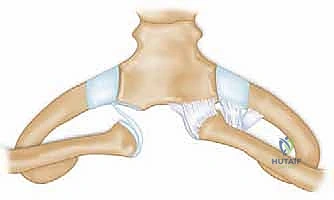

لا يمكن ببساطة خياطة الأربطة الممزقة لضمان الاستقرار. لذلك، يستخدم الدكتور هطيف تقنية متقدمة لإعادة البناء باستخدام "رقعة وترية" (Tendon Graft).

* حفر الأنفاق العظمية: يتم حفر ثقوب دقيقة جداً في عظم الترقوة وعظم القص باستخدام أدوات جراحية متطورة.

5. تمرير الرقعة وتثبيتها (تقنية الرقم 8)

يتم تمرير الرقعة الوترية عبر الثقوب العظمية بنمط يشبه الرقم 8 (Figure-of-eight). هذه التقنية الميكانيكية الحيوية توفر قوة استقرار هائلة تحاكي قوة الأربطة الطبيعية (الرباط الكبسولي والرباط الضلعي الترقوي).

تحذير طبي هام: في الماضي، كان بعض الجراحين يستخدمون أسياخ معدنية (K-wires) لتثبيت المفصل. الأستاذ الدكتور محمد هطيف يمنع تماماً استخدام هذه الأسياخ في هذا المفصل، حيث أثبتت الدراسات الطبية أن هذه الأسياخ قد تهاجر وتخترق القلب أو الرئتين مسببة الوفاة. بدلاً من ذلك، يعتمد الدكتور هطيف على خيوط جراحية فائقة القوة (Suture anchors) والرقع الوترية الطبيعية التي تندمج مع الجسم.